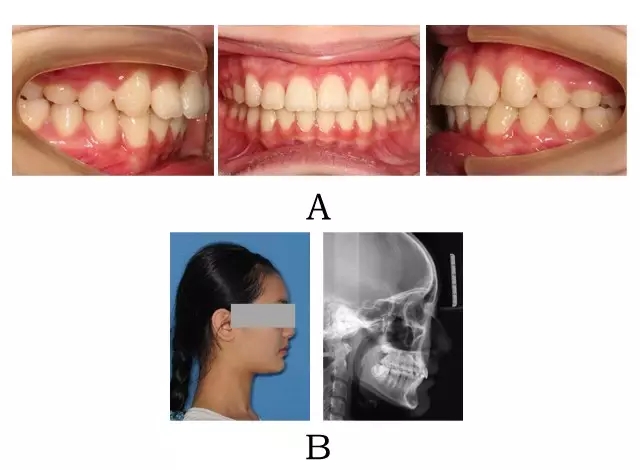

圖 3-3:頜位性突面畸形矯形治療臨床療效及頭顱側(cè)位影像變化。

(A) 咬合改善 (B) 側(cè)貌改變

Figure 3-3. Treatment outcomes for mandibular positional prognathism. (A) Occlusion correction. (B) Facial esthetic improvement.